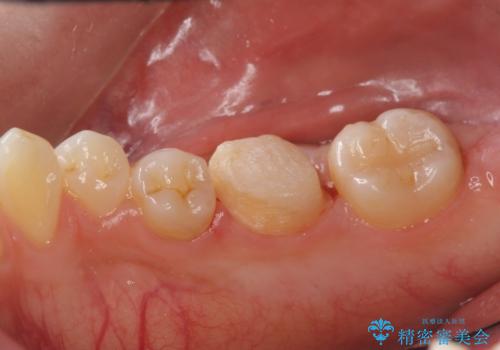

- 他院で入れたセラミックインレーが欠けてしまい来院。

やり直しに当たって、以下の提案を行い選んで頂いた。

①同様にセラミックインレーのやりかえ

→欠けたところが上の歯と噛み込んでおり、そのままやりかえるとさらに歯が薄くなり、また欠けてしまうリスクが高い状態

②ゴールドアンレーに変更する

→欠けた部分をしっかり覆うことができる。薄い歯質の部分がなくなり、歯は割れにくくなる。

ただし、金属になるため審美性は①より劣る。

③ジルコニアクラウンで被せる

ただし、①②よりも歯を大きく削ることになる。

ジルコニアクラウンは白いため、審美性は保たれる。

患者と相談し、金属よりも白いものを入れたい、また、もう歯が欠けてやり直すのは嫌だとのご希望だった。

そのため、歯質の削除量は増えるが、クラウンで被せる③の方針で行くことになった。